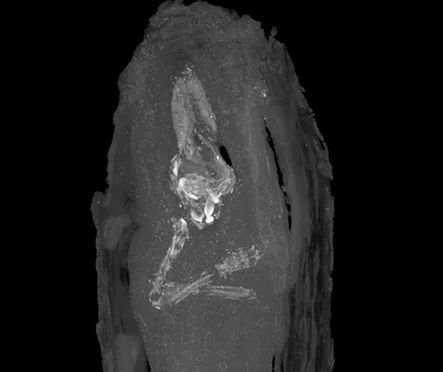

“The images revealed a tiny human body, wrapped in bandages sealed with black resin. The long bones of the legs and arms are visible, as are five digits on both hands and feet. The soft skull and pelvis appear to have collapsed, but despite the damage, curators could put the age of the foetus at no more than 18 weeks gestation.”

The arms were crossed over the chest, like in traditional Egyptian fashion, which indicates how important this fetus was.